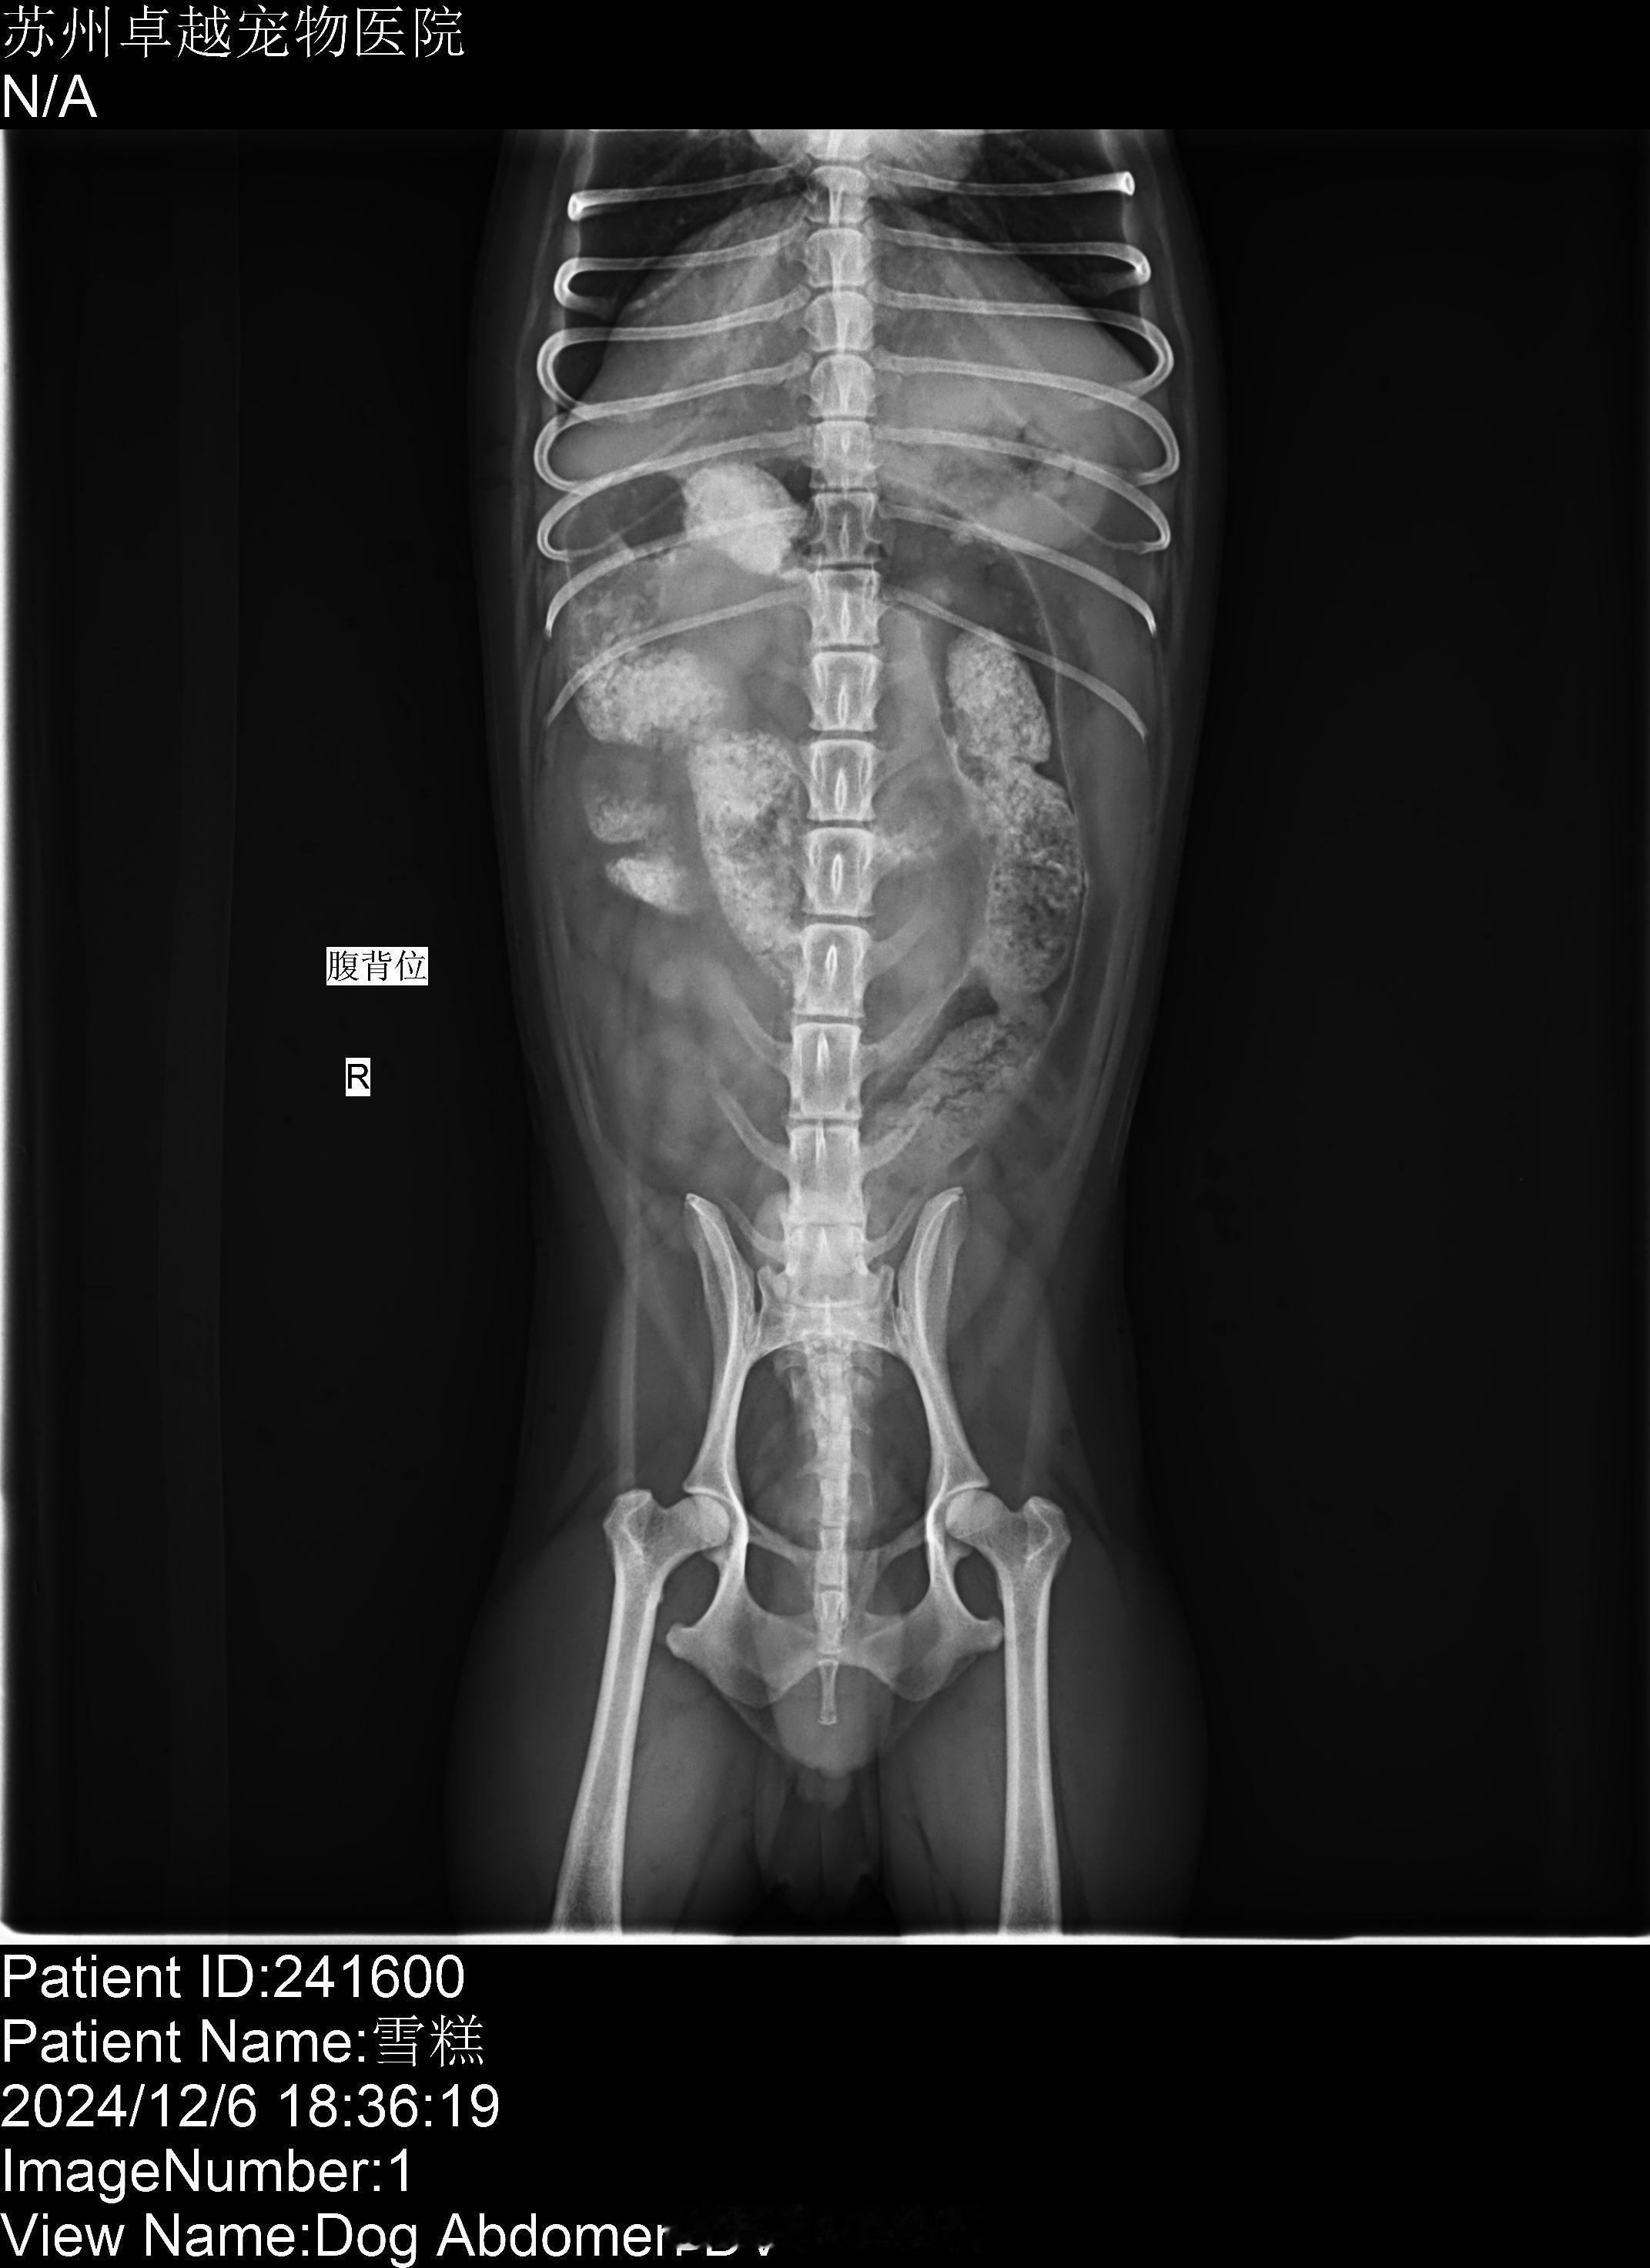

吃骨头的狗狗胰腺炎[泪][泪]

肠道也堵住了。

苏州卓越宠物医院